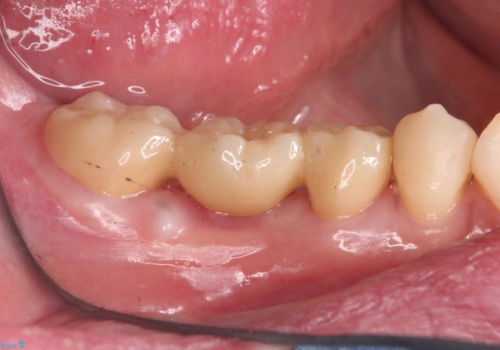

歯がなくなったところに関しては、ブリッジで修復することにしました。

- 26.2万円(ヴェレッツァクラウン 7.7万円×3本 仮歯 1.1万円×3本)費用は治療当時の料金となります

初めての根の治療には見えないくらい、かなり歯が削ってあり、薄くなっていて割れても仕方ない状態でした。前の状態を見ていないので何とも言い難いですが、他の歯に比べこの歯だけ極端に状態が悪かったです。

当院は最後まで歯を残せるように、きちんと破折していないかチェックし、患者様に写真を確認していただいたうえで抜歯をするかを相談していきます。